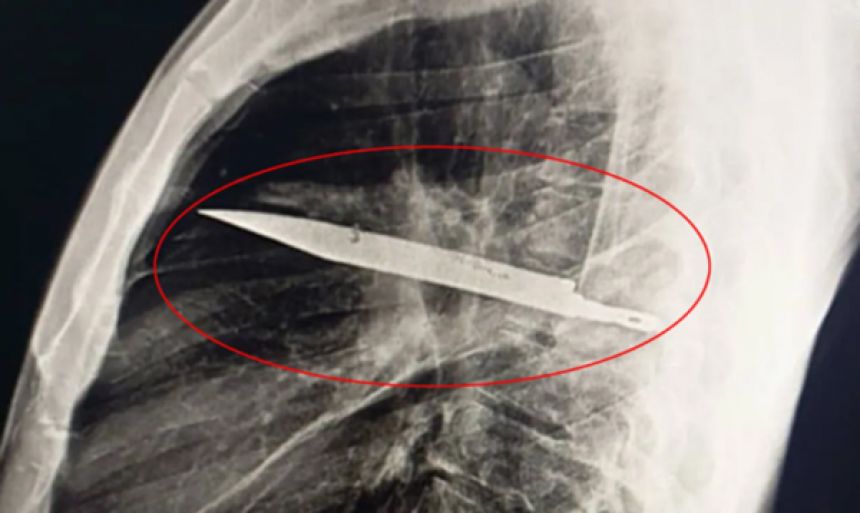

この画像を大きなサイズで見る東アフリカ・タンザニアで、胸の中にナイフの刃が刺さったまま、8年間も何ごともなかったかのように暮らしていた男性がいた。しかもその間、咳も発熱もなく、ふつうに働き、食べて眠り、日常を送っていたというのだから驚きだ。

事態が発覚したのは、わずか10日前。胸の痛みと右乳首から膿が出る症状が現れた男性が病院を受診し、胸部のX線検査を受けたところ、胸の中央にナイフの刃がくっきりと映し出された。

何かしらの皮膚感染や内出血が疑われたが、胸部X線検査の結果、医師たちは驚愕する。胸の中央、ちょうど胸骨の裏あたりに、金属のような異物がくっきりと写っていたのだ。

精密な画像診断により、それがナイフの刃であることが明らかとなる。

そのナイフの刃は、おそらく数インチ(数cm)ほどの長さとみられており、胸の奥深くに潜り込むように刺さっていた。

最も驚くべき点は、その刃が心臓や肺といった生命に直結する臓器を、避けるかのように刺さっていたことだった。

なお、症例報告にはナイフの正確な大きさの記載はないが、CT画像や肋間の広がりから推定すると、少なくとも10cm程度の長さがあった可能性がある。